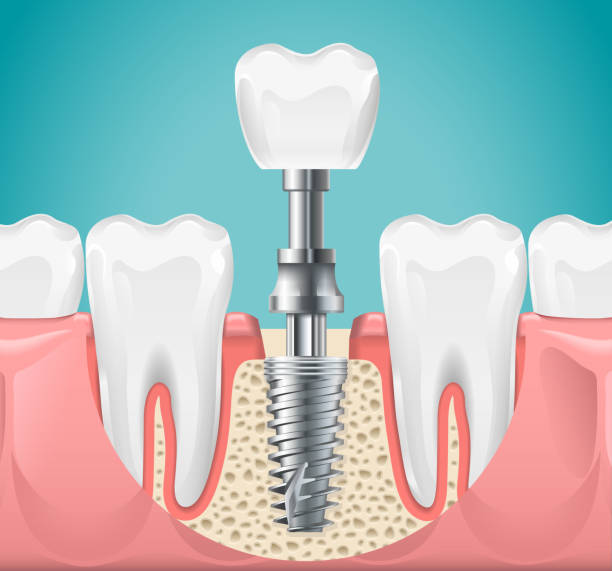

فکرشو بکنید، یه عفونت کوچیک توی ریشه دندون میتونه کل سیستم بدنتون رو به هم بریزه. اگه بهش بیتوجهی کنین، ممکنه حتی استخوان فک رو هم درگیر کنه یا حتی، خدای نکرده، منجر به مشکلات جدیتر سلامتی بشه. هدف اصلی از عصب کشی، پاک کردن اون عفونت از مغز دندون (پالپ) و کانالهای ریشهست. اینجوری هم درد از بین میره، هم دندون عزیزتون برای سالها باقی میمونه و نیاز به کشیدن پیدا نمیکنه. خیلی از ما هنوز تصوری قدیمی و دردناک از این درمان داریم، در حالی که با پیشرفتهای امروزی و تکنیکهای نوین، عصب کشی دندان اصلاً اون چیزی نیست که قدیمها بوده. دردش هم با بیحسیهای موضعی تقریباً از بین میره.

یادتونه گفتم مراحل عصب کشی دندان با تصویر ذهنی؟ خب، حالا بیایید دقیقتر ببینیم توی مطب، چه اتفاقاتی میفته. این جوری کمتر اضطراب میگیرید و میدونید دقیقاً قراره چی بشه. اول از همه، دندانپزشک یه بیحسی موضعی قوی بهتون تزریق میکنه تا هیچ دردی رو حس نکنید. این مرحله واقعاً مهمه و حسابی دندون و لثه اطرافش رو کرخت میکنه. بعدش، با استفاده از یه پرده لاستیکی (که بهش رابر دم میگن) دور دندون رو ایزوله میکنه تا دندون از بزاق دهان جدا بشه و میکروبهای دهان وارد فضای درمان نشن. این خیلی تو جلوگیری از عفونت مجدد مؤثره.

مرحله بعدی، ایجاد یه سوراخ کوچیک توی تاج دندونه تا دندانپزشک به پالپ و کانالهای ریشه دسترسی پیدا کنه. نگران نباشید، این سوراخ بعداً پر میشه. حالا نوبت به پاکسازی میرسه. دندانپزشک با ابزارهای مخصوص و بسیار ریز (فایلهای دندانی) و محلولهای شستوشو، بافت عفونی و پالپ آسیبدیده رو از داخل کانالها خارج میکنه. این مرحله ممکنه کمی طول بکشه، چون باید مطمئن شد که همه عفونت از بین رفته. در سلامت کاشت درین، ما ابزارهایی مثل فایلهای اندو و موتورهای ایمپلنت (که در عین حال برای آمادهسازی کانال ریشه نیز میتوانند استفاده شوند) را عرضه میکنیم که نشاندهنده تعهد ما به کیفیت ابزار دندانپزشکی است.

بعد از پاکسازی و شکلدهی کانالها، نوبت به پر کردن اونها میرسه. معمولاً از مادهای به اسم گوتاپرکا که شبیه لاستیکه، استفاده میشه. این ماده به همراه یه چسب مخصوص، کانالها رو کاملاً مهر و موم میکنه تا میکروبها نتونن دوباره وارد بشن. در نهایت، روی دندون یه پانسمان موقت میذارن یا اگه دندون خیلی آسیب ندیده باشه، یه پرکردگی دائمی انجام میشه. همینجوری که میبینید، هر گام با دقت و وسواس خاصی انجام میشه تا نتیجه درمان بهترین باشه. این فرایند معمولاً در یک یا دو جلسه انجام میشه، بستگی به میزان پیچیدگی و عفونت دندان داره. این جدول به شما کمک میکنه یک دید کلی از این فرآیند داشته باشید:

👑 تاج دندانی: سپر دفاعی دندان عصب کشی شده

بعد از اینکه مراحل اولیه عصب کشی دندان با موفقیت طی شد و دندان شما از شر عفونت خلاص شد، تازه نوبت میرسه به یه مرحله فوقالعاده مهم دیگه: قرار دادن تاج دندانی یا همون روکش. شاید فکر کنید خب دندون که دیگه خوب شده، چرا روکش لازمه؟ اینجا یه نکته کلیدی وجود داره که خیلیها ازش غافلند. دندونی که عصب کشی میشه، دیگه اون خونرسانی و تغذیه طبیعی رو نداره و به مرور زمان خشکتر و شکنندهتر میشه. مثل یه شاخه درخت که از تنه جدا شده، هرچقدر هم سالم به نظر بیاد، در نهایت خشک میشه و با کوچکترین فشاری میشکنه.

روکش دندان، مثل یه کلاه ایمنی برای دندون عصب کشی شده عمل میکنه. این کلاه مقاوم، کل سطح دندون رو میپوشونه و ازش در برابر فشارهای جویدن، شکستگی یا ترک خوردگی محافظت میکنه. بدون روکش، احتمال اینکه دندون شما بعد از عصب کشی بشکنه، خیلی خیلی بیشتره و ممکنه مجبور بشید دندون رو از دست بدید و بعداً به فکر ایمپلنت دندانی بیفتید. اینجا جاییه که پروتزهای دندانی باکیفیت اهمیت خودشون رو نشون میدن.